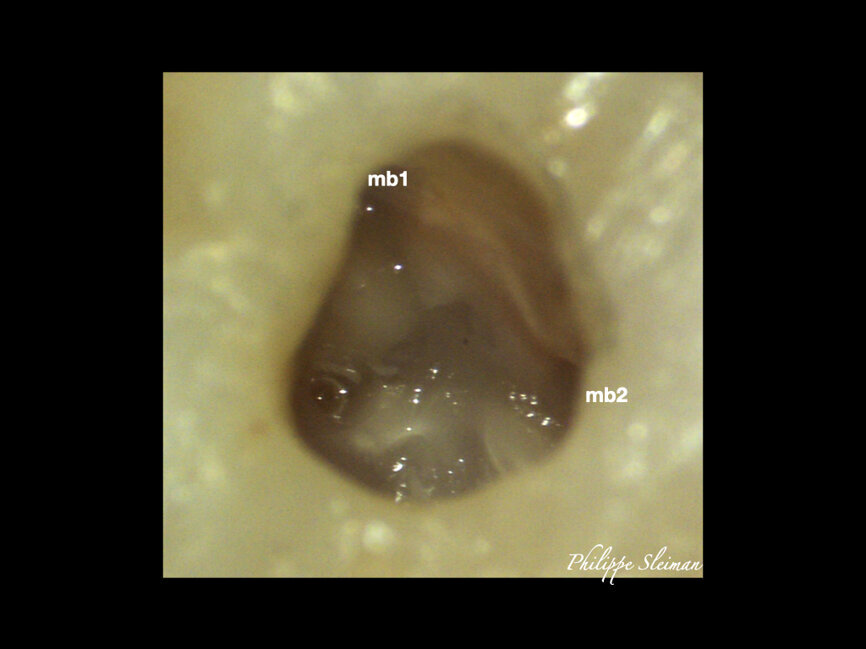

The preoperative radiograph (Fig. 1) revealed that the roots had an uncommon shape, particularly regarding the palatal root, the periodontal ligament and the apex of the mesial root. Upon creating the access cavity (Fig. 2), under the operating microscope, I noticed bleeding from the mesiopalatal angle. Extending the access cavity to that side led to the discovery of a separate canal, which may have been a second palatal or an independent mesial canal.